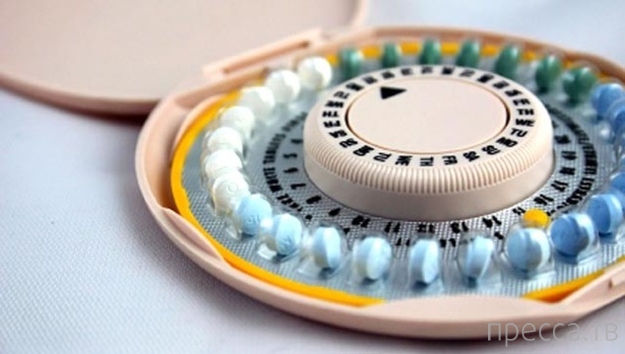

11. Противозачаточные таблетки (1957)

Хотя изобретение этих таблеток обычно относят к сексуальной революции 60-х, но в действительности они появились ещё в 50-е. Управление по контролю качества пищевых продуктов и лекарственных препаратов одобрило эти таблетки в 1957 году, но только для случаев тяжёлого нарушения менструального цикла, а не как контрацептив. До 1960 года таблетки официально не признавались противозачаточным средством.